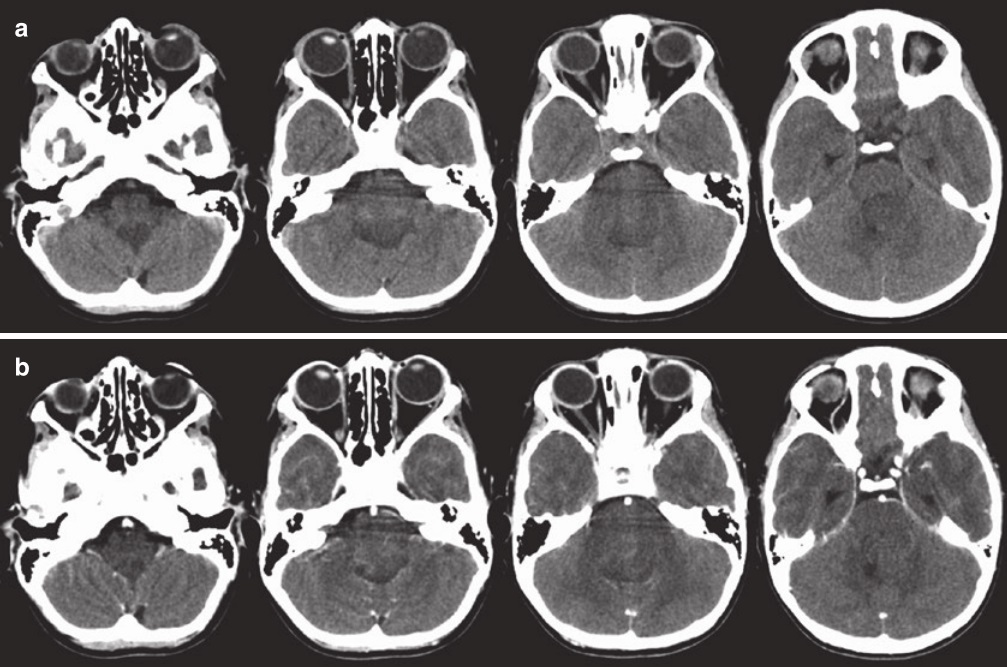

图4:一名12岁男孩背侧外生脑干胶质瘤的CT扫描,有5个月的病史,逐渐加重的肢体笨拙、共济失调和复视。(a)无对比的轴位CT扫描显示填充四脑室的轻微低密度病变。(b)对比剂给药后,病灶呈斑片状、不均匀强化。背侧脑干病变边界没有得到很好地显示

CT扫描仍可用作快速筛查工具。在CT上,这些病变通常是低密度的并充满四脑室。明亮的强化也可能很明显(图20.9)。MRI已成为用于背侧外生性脑干胶质瘤儿童的标准评估工具。在MRI上,可以在背外侧看到周围脑脊液的帽状结构。在腹侧,肿瘤会融入脑干,通常很难确定肿瘤在哪里结束,脑干的功能部分从哪里开始。信号特征为T1序列低信号,T2序列高信号。与弥漫内生型病变相比,T1和T2的肿瘤边缘通常是一致的,而与T1序列相比,T2序列通常有更大范围的信号异常区域。与CT一样,静脉注射造影剂后可见明亮的强化(图5)。

图5:背侧外生脑干胶质瘤的MRI扫描。(a)轴位T1 MRI显示病灶与四脑室底直接相对。(b)轴位T2 MRI显示四脑室中的高信号病变。(c)轴位T1 MRI对比显示病变有些斑片状强化。(d)矢状位T1 MRI对比CT显示肿瘤与四脑室底部的关系,分辨率高于CT

2.诊断方法:选择的成像方式是核磁共振。在对比剂增强后,被盖肿瘤通常均匀强化(图4)。他们可以很大体积地占据整个被盖部,并且可因Monro孔闭塞而引起脑积水。